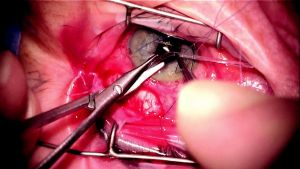

Trimming the Tube

Corneal traction is released so that the eye can return to its normal position and the surgeon can determine the optimal location to trim the tube. Release of corneal traction is important because if the surgeon trims the tube while the eye is torqued inferonasally without accounting for this, the tip of the tube may end up too long in the anterior chamber after traction is released. If the tube needs to be rerouted around scar tissue, this should be taken into consideration when deciding the location to trim the tube, as it may need to be longer to account for such rerouting. With the nondominant hand, the tube is grasped with tying forceps and Westcott or Vannas scissors are used with the dominant hand to trim the tube in a manner so that a sharp bevel is created (Figure 8-3). It is important not to forcefully tug the tube toward the center of the cornea when grasping it with the nondominant hand prior to trimming it, as this can cause the surgeon to inadvertently trim the tube so that it is too short. When trimming the tube, one should err on the side of too long rather than too short. If it is too long, it can always be trimmed shorter, whereas if the tube is trimmed too short, a tube extender may be required to lengthen it.